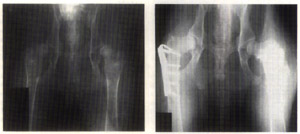

Prior to improvements in the method for performing triple pelvic osteotomy, the intertrochanteric osteotomy was commonly used if there was adequate depth in the acetabulum socket, and if the dorsal rim was normal, i.e., osteophyte formation had not begun.8 This surgery reduces the angle of the femoral neck, which improves congruity between the femoral head and the acetabulum, resulting in an improved fit. Because it corrects conformational and structural problems of the femoral head, this procedure must be performed before any major remodeling of the acetabulum has occurred. Nevertheless, pain and radiographic subluxation must be clinically evident prior to any reconstructive surgery in order to justify the pain, effort and expense. The average angle of inclination of the femoral neck in the dog is 149 degrees(normal range 141 to 157 degrees). The intertrochanteric osteotomy over-corrects this angle to approximately 135 degrees by removing a wedge of bone. See Figure 5 and Figure 6 for before and after images. This is thought to increase the surface area over which the pressure or "load" is spread. The greater the surface area, the less the pressure per unit of area there is on the coxofemoral joint in any one place.

Figure 5 (left) shows before and Figure 6 (right) shows after double intertrochanteric osteotomy. Note the improved congruity between the femoral head and acetabulum. Photos courtesy of Braden, T.D.; Prieur, W.D. "Three plane intertrochanteric osteotomy for treatment of early stage hip dysplasia." Vet Cl N Am Sm Anim Prac. Vol.22 No.3 May 1992. pp.624-643.